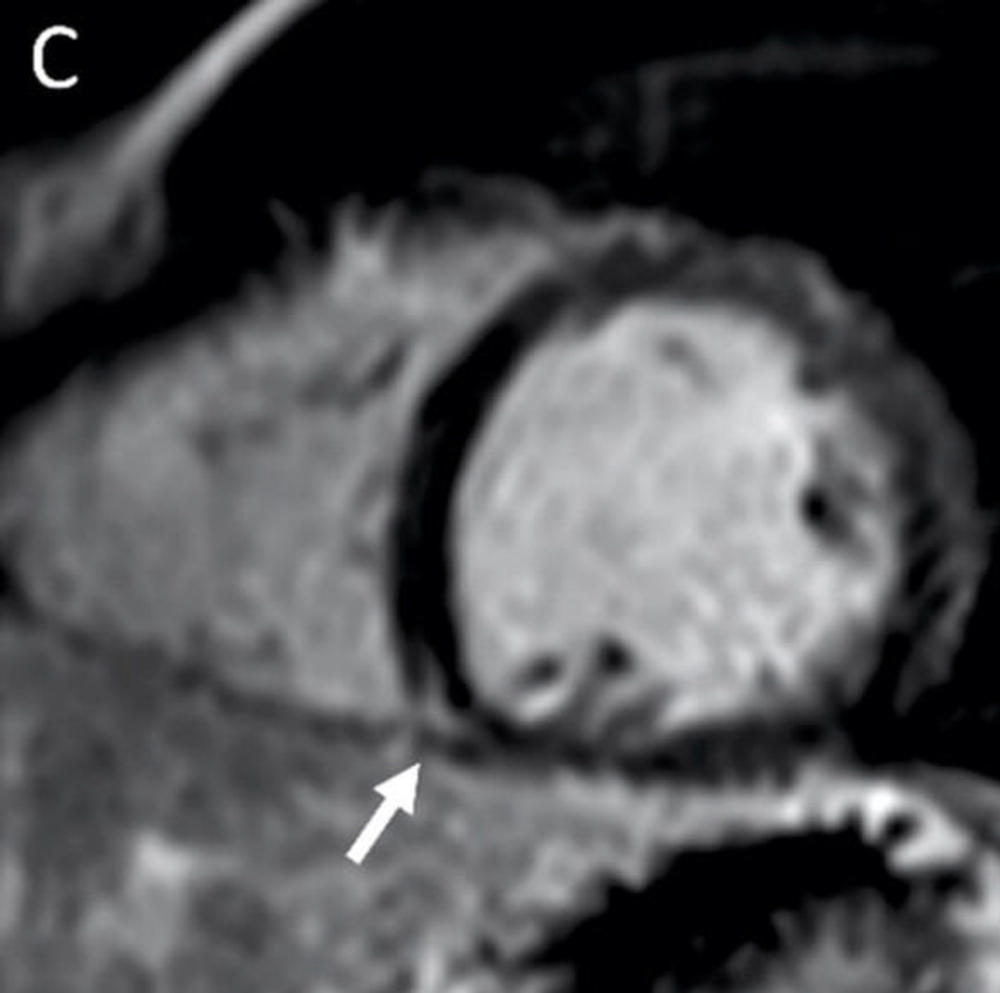

Figure 1. MRI shows late gadolinium enhancement (LGE) at the right ventricular attachment (arrow) of a 19-year-old male. Note: this image is for illustrative purposes only and is not associated with the Big Ten study group. Image courtesy of Radiology.